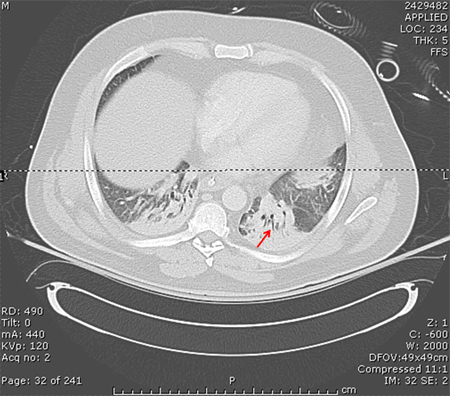

tomografia computadorizada (TC) do tórax

Uma tomografia computadorizada (TC) pode ser realizada para diagnosticar a opacidade e esclarecer se um procedimento é indicado.[Figure caption and citation for the preceding image starts]: Tomografia computadorizada mostrando opacidades bibasilares de paciente com pneumonia hospitalarConsentimento obtido na University of Louisville, Louisville, KY [Citation ends].

[Figure caption and citation for the preceding image starts]: TC de paciente com um infiltrado no lobo inferior esquerdo (seta azul), derrames pleurais bilaterais (pontas de seta amarelas) e atelectasia basilar direita; note a linha separando as duas sombras de cinza, representando o infiltrado e o fluidoConsentimento obtido na University of Louisville, Louisville, KY [Citation ends].

Resultado

pode mostrar opacidade ou esclarecer achados prévios quando a qualidade da radiografia for insatisfatória